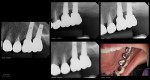

13 years on a tooth which shouldn’t have made it

Collage-2140635390-Page00